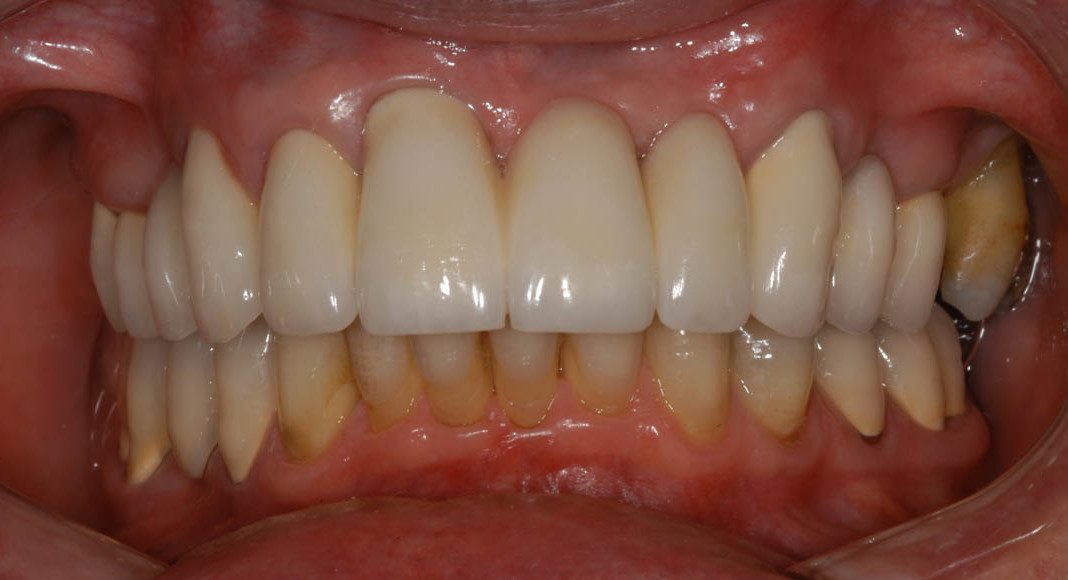

Pre-treatment, lips retracted. Notice the exposed roots on several of the back teeth, and the metal margins around some of the crowns? Also, she did not like the gum line above her two front teeth being uneven.